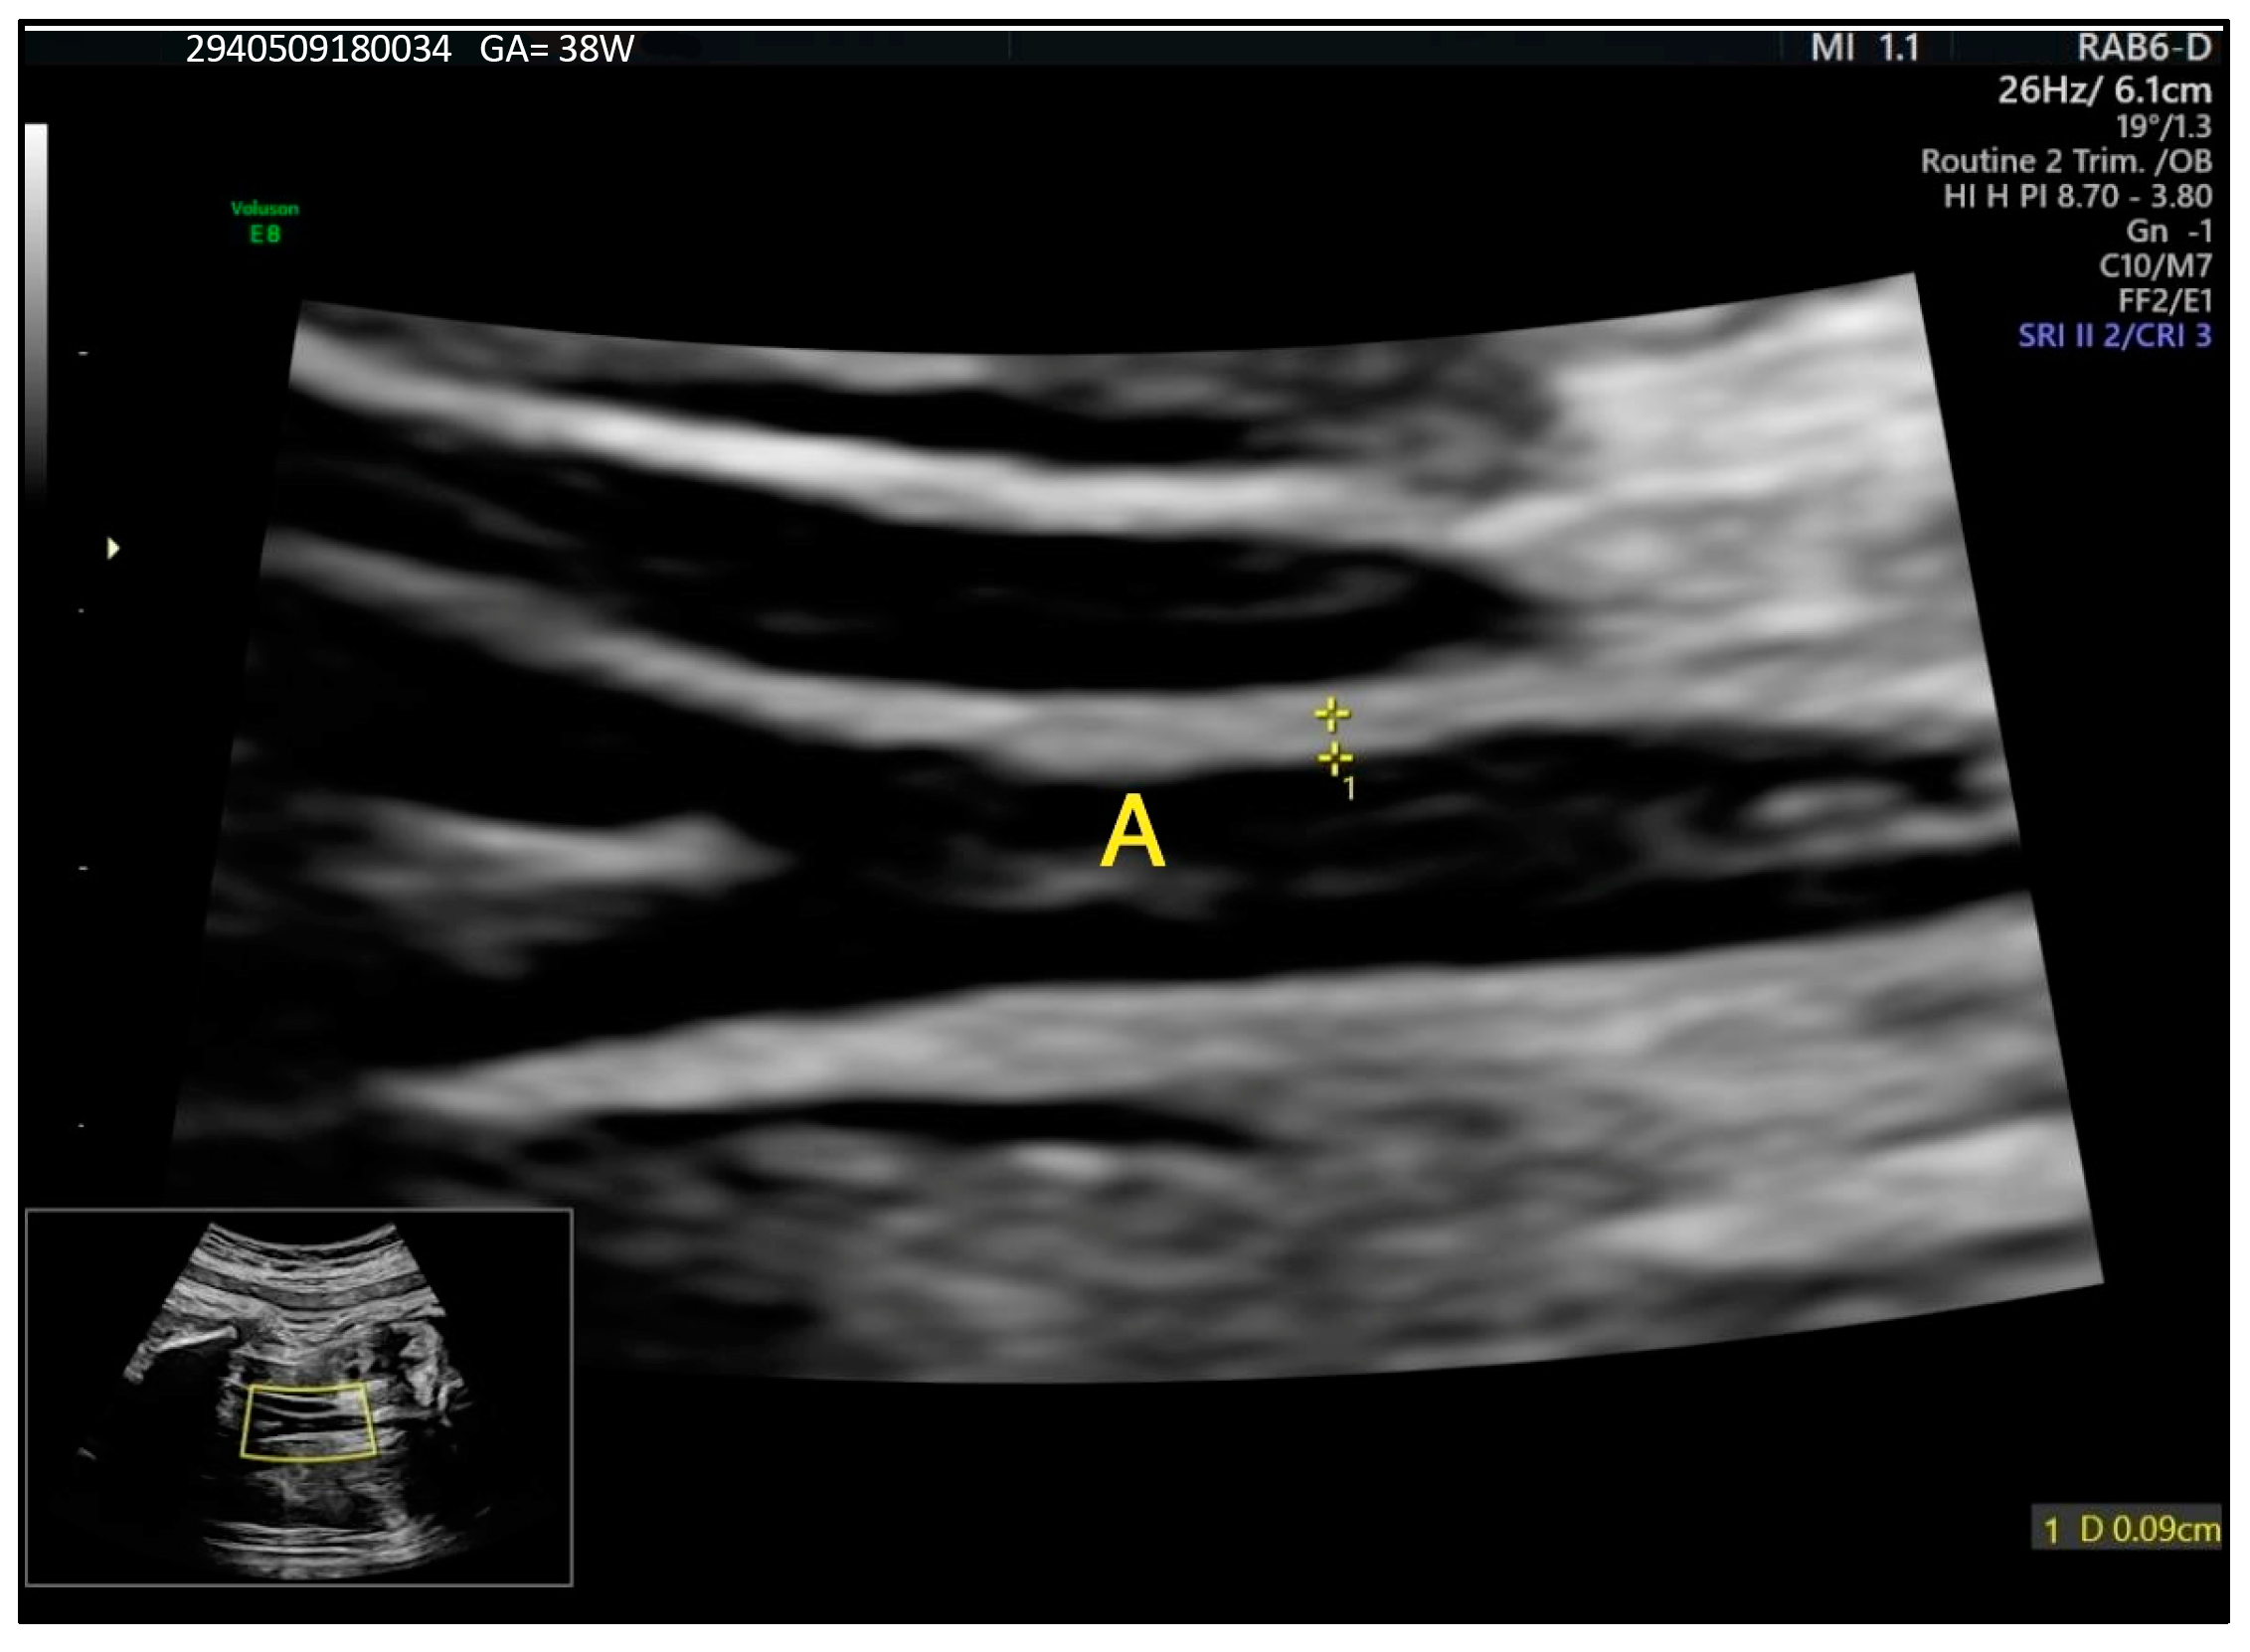

Evaluating Maternal Risk Factors Impacting Fetal Intima–Media Thickness of the Abdominal Aorta Measured at 28 Weeks of Gestation

2. Materials and Methods